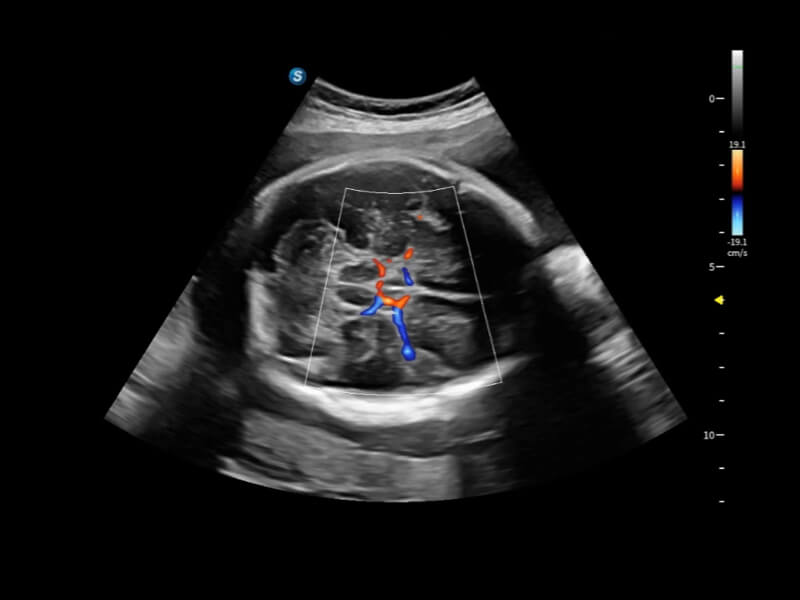

豐富的血流動(dòng)力學(xué)檢測(cè)技術(shù),可在不同醫(yī)療場(chǎng)景中高效捕捉血流信號(hào),助力臨床診療。

在傳統(tǒng)血流的基礎(chǔ)上優(yōu)化掃查和算法策略,能夠更好的抑制組織信息,提煉紅細(xì)胞運(yùn)動(dòng)信息,得到更高幀頻,高靈敏度和分辨率的血流信號(hào),還原更真實(shí)的血流動(dòng)力學(xué)。

通過(guò)光照模型,使二維血流顯示出立體的效果,增加血流的敏感性、成束性,減少外溢??梢院推渌煌难骷夹g(shù)聯(lián)合使用,融合不同技術(shù)的優(yōu)勢(shì)。輕松應(yīng)對(duì)微小血管,增強(qiáng)血流的立體效果,提升視覺(jué)敏感性。